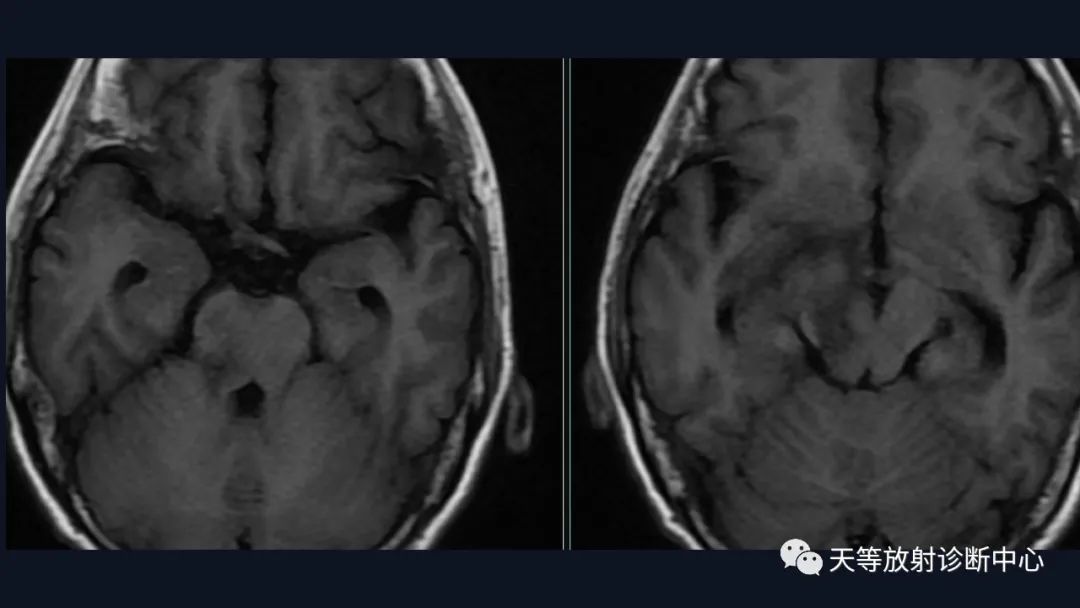

脑内占位的特点:

1、刀切征

2、凹陷征或肚脐凹征

3、尖角征

4、多发

5、DWI呈稍高信号

6、形态上怪异

6、NAA及Cho减低,出现导致LL峰。

结合颈部、胸廓入口区及腋窝多发淋巴结肿大并相互融合。

综合考虑淋巴瘤